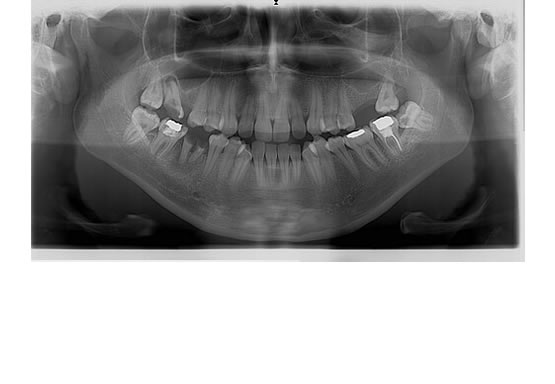

Panoramik Görüntüleme

Panaromik röntgen, çenelerin, tüm dişlerin, çene ve dişlerdeki bir çok rahatsızlığın tek bir filmde görülmesini sağlayan röntgen filmleridir.